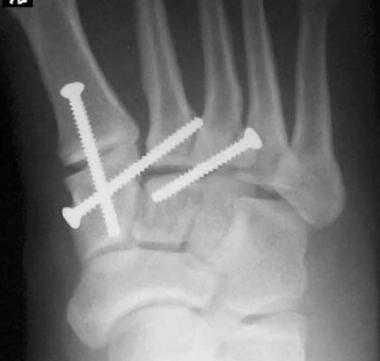

При смещении более 2 мм, нестабильности при функциональных тестах - рекомендовано открытое устранение вывиха с жёсткой фиксацией винтами или пластинами. Используются один или два продольных доступа в 1 и 2 межплюсневых промежутках. После обнажения первого предплюсне-плюсневого сустава первым этапом устраняется межклиновидная нестабильность, вторым этапом устраняется предплюсне-плюсневая нестабильность. В послеоперационном периоде сразу начинается разработка активного объёма движений. Нагрузку на стопу начинают постепенно, с тем чтобы полностью её восстановить к 6-8 неделе. Удаление спиц Киршнера производится через 6-8 недель, компрессирующих винтов через 3-6 месяцев. Возвращение к полной физической активности не ранее 9-12 месяцев после операции.

Открытое вправление вывиха, трансартикулярная фиксация 1-2-3 предплюсне-плюсневых суставов винтами.

После осмотра в отделении ортопедии №2 ГКБ №13 принято решение о проведении операции - открытому устранению вывиха, артродезе 1-2-3 плюсне-клиновидных суставов, 1 межклиновидного сустава при помощи винтов и пластины, трансартикулярной фиксации спицами 4-5 плюсне-клиновидных суставов.

Вершиной, ключом, блокирующим клином - в общем главной частью сустава Лисфранка является 2 плюсне-клиновидный сустав. По этой причине мы предпочитаем начинать фиксацию именно с него. Для артродеза используем винты с направленной в разные стороны резьбой FT Arthrex диаметром 4 мм. Они позволяют создать мощную межфрагментарную компрессию, а за счёт глубокой резьбы очень надёжно фиксируются в кости.

После восстановления 2 луча выполняем артродез межклиновидного сустава и 1 плюсне-клиновидного сустава. Учитывая что основная нагрузка ложится на 1 луч, дополнительно стабилизируем его при помощи пластины.